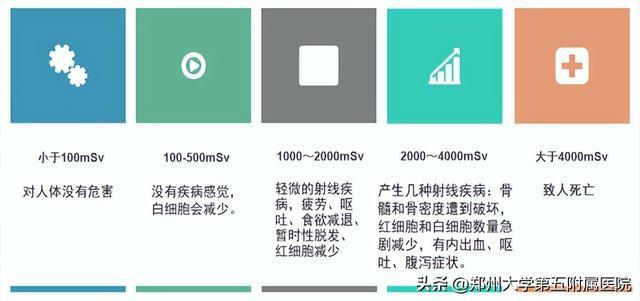

有輻射的檢查還敢做

輻射其實沒那麼可怕!

我們每個人每天都在接受來自宇宙射線和自然界天然放射性核素髮出的電離輻射,稱本底輻射。因各地地表放射性物質含量不同,劑量約2.4~6.0mSv/年。目前研究表明,本底輻射水平對人體健康沒有影響。

根據《電離輻射防護與輻射源安全基本標準GB18871-2002》人體可接受的年輻射劑量限值為50mSv。

06如何降低輻射危害

Ø 輻射實踐正當化

在施行伴有輻射照射的任何實踐之前要經過充分論證,權衡利弊。只有當該項所帶來的社會總利益大於為其所付出的代價的時候,才認為該項實踐是正當的。

Ø 輻射防護最優化

(As Low As Reasonably Achievable,ALARA,合理可能儘量低)在實際的輻射防護中占有重要的地位。在實施某項輻射實踐的過程中,可能有幾個方案可供選擇,在對幾個方案進行選擇時,應當運用最優化程序,也就是在考慮了經濟和社會等因素後,應當將一切輻射照射保持在可合理達到的儘可能低的水平。

Ø 個人劑量當量限值

個人所受的照射必須符合劑量限值,確保沒有人需要接收不能承受的輻射危害。